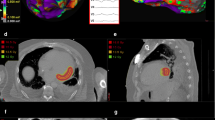

During the follow-up period, four patients died. Reasons for death were COVID-19 sepsis in two patients, gastric cancer in one patient, and end-stage heart failure with recurrent VT in one patient. One patient (case 1) underwent cardiac transplantation at the 12th months after SBRT session. The workflow for SBRT and tissue level examination findings are showed in Fig. 2.

Stereotactic body radioablation therapy workflow and tissue level examination findings in the same patient. Delineation of the internal gross target volume (IGTV) (pink line) and planning target volume (PTV) (red line) that included the full thickness of the myocardium in integrated images from the PET-CT (A) and 4D CBCT (B) using mechanical valves and defibrillator lead for alignment in the axial, coronal, and sagittal views. Apical part of the septum was especially covered because of presumed intramural substrate inaccessible with epicardial approach. Isodose distribution of PTV with delivered dose of 2500 cGy (25 Gy) with doses at least 95% of 25 Gy in the planned target volume and with doses in excess of 25 Gy (110% of 25 Gy) displayed in the color spectrum (C). Device interrogation showing VT episodes before and after SBRT procedure demonstrating no ICD shocks in the first 6 months with following recurrences after this time (red arrow) (D). Macroscopic view of the left ventricle explanted after stereotactic body radiation therapy (E). White areas demonstrate fibrosis from SBRT. Microscopic view of the left ventricle explanted after stereotactic body radiation therapy (F). SBRT causes extensive myocardial interstitial fibrosis with hematoxylin–eosin. Remaining areas demonstrate hypertrophic cardiomyopathy